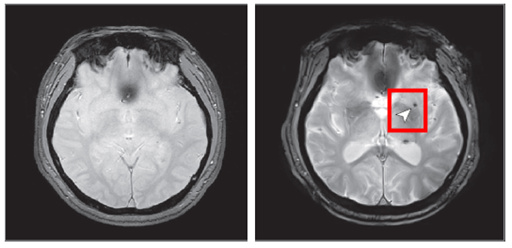

연구에 따르면 수면무호흡증이 없는 사람들의 뇌 미세출혈 발생률은 3.3% 수준이었지만, 중등도 이상의 수면무호흡증 환자에게서는 이 비율이 7.25%로 뛰어올라 약 2.14배 증가한 것으로 나타났다. 즉, 시간이 지날수록 반복되는 수면 중 호흡정지가 뇌 혈관을 직접 손상시킬 수 있다는 의미다.

뇌 미세출혈은 뇌 속 작은 혈관이 손상돼 발생하는 미세한 출혈로, 향후 뇌졸중 등 심각한 혈관 질환을 예고하는 초기 지표로 알려져 있다.